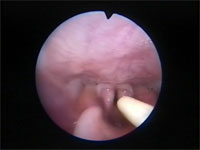

Abb 1 Kehlkopf-offen

Abbildung 1: Larynx der Katze. Rima glottidis (oben) und Plica vocalis sind geöffnet.

Der Larynx funktioniert wie eine Klappe zwischen den oberen und unteren Atemwegen. Seine wichtigsten Funktionen sind der Schutz der unteren Atemwege vor der Inhalation von Fremdkörpern, die Kontrolle des Atemwegdurchmessers während des Atmungszyklus und die Stimmbildung. Die Kehlkopftasche (Ventriculus laryngis) fehlt bei der Katze. Dorsal der Processi cuneiformes der beiden Aryknorpel befindet sich eine bei der Katze eine kleine schmal ovale Öffnung, die als Stimmritze (Rima glottidis) bezeichnet wird. Der Durchmesser der Stimmritze wird durch die Lage und Länge der Stimmfalten bestimmt, die wiederum von der Lage der Aryknorpel abhängen. Eine dorsolaterale Bewegung der Aryknorpel zieht die Stimmfalten auseinander und sorgt damit für eine Erweiterung der Stimmritze. Eine mediane Bewegung führt zu einer Verengung der Stimmritze bis auf eine schlitzartige Öffnung oder zu deren vollständigem Verschluss.